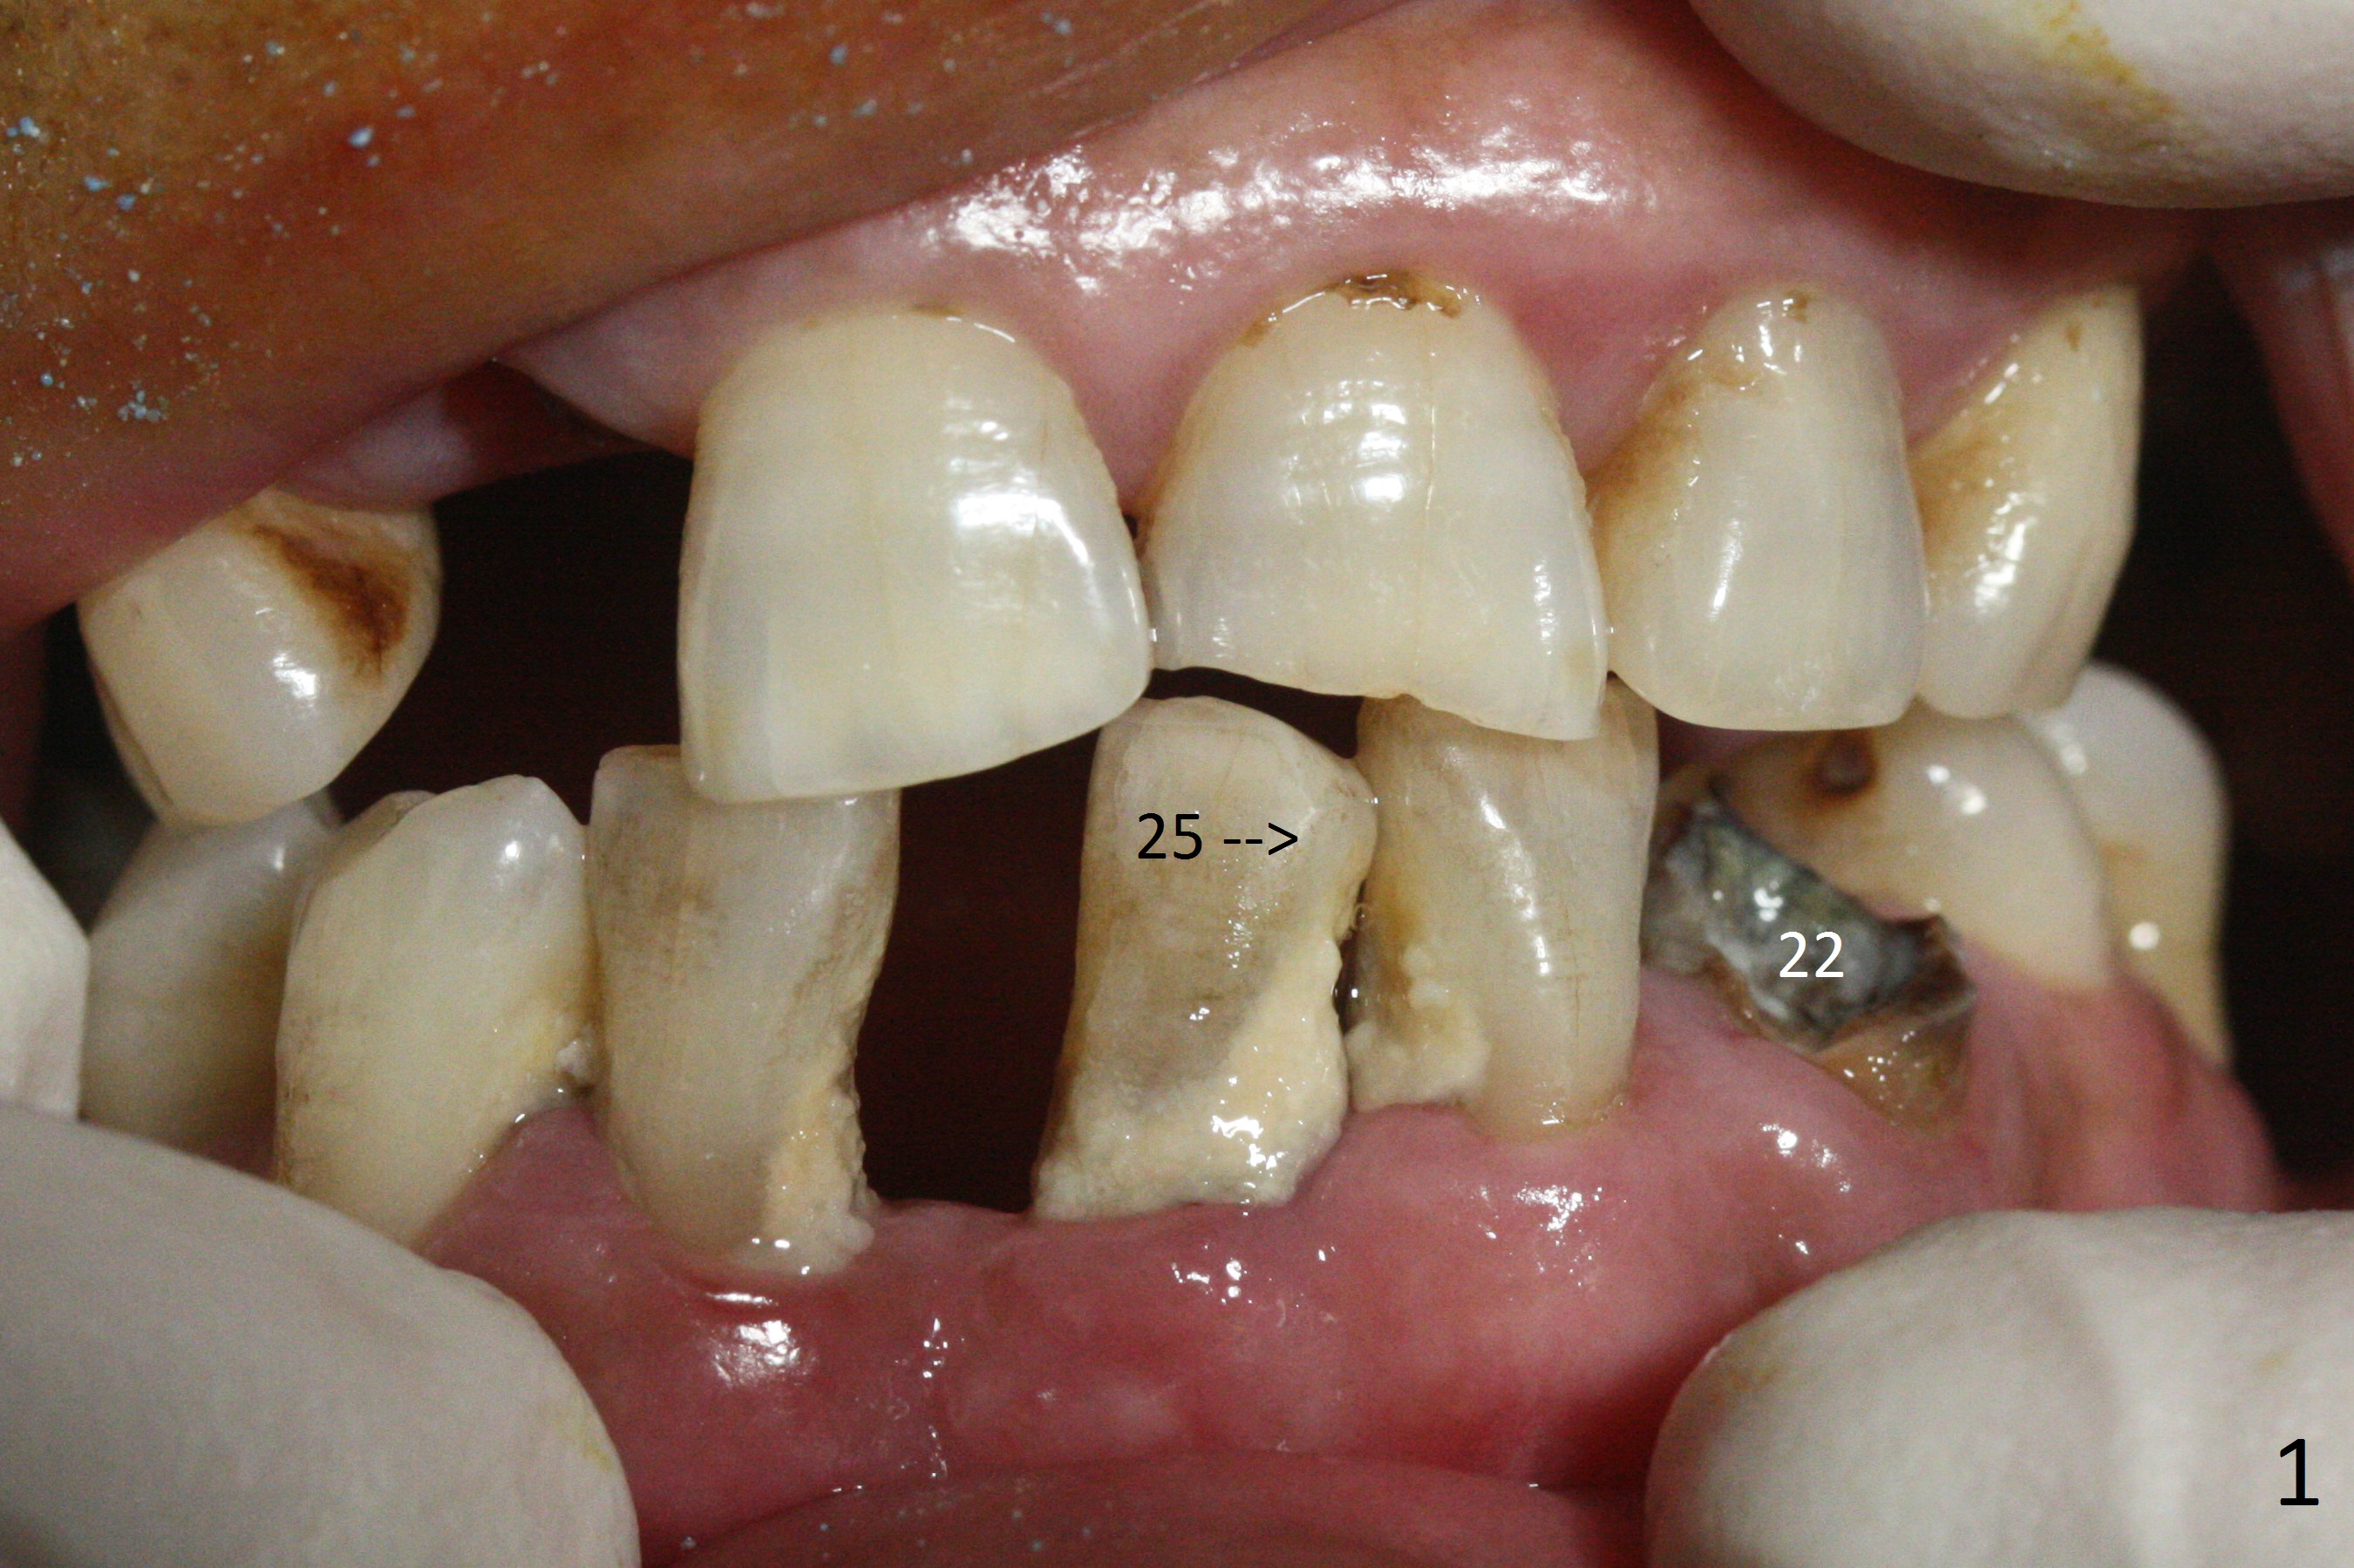

Before surgery, the patient reports that the tooth #25 has inclined to the position of #24 since the latter was extracted (Fig.1). After extraction of the tooth #25, there seems to be more bone vertically at the site of #24 than that of #25. Therefore the osteotomy is initiated at #24. The edentulous space is 9 mm mesiodistally, whereas the incisor width is 6 mm. The first pilot drill is fractured (1.2 mm). The latter is retrieved with incision. With better visibility, the initial osteotomy is found buccal. When a 3x14(2) mm dummy 1-piece implant is being placed partially, the buccal plate seems to be thin. A 2.5x14(4) mm 1-piece implant is placed instead with stability (Fig.2).

The depth of the osteotomy at #22 is 2-3 mm more than the expected implant length (Fig.2 with 2.7 mm drill in place). The implant at #22 (3.8x18 mm with insertion torque more than 50 Ncm) has clearance from the Incisive Canal and Mental Loop (Fig.3 red dashed line). Allograft with Osteogen is placed around the implants (Fig.4 *) in addition to Osteogen plug (cut in a thin layer) placed against the buccal wall of the socket at #22 (potential leakage). After suturing (Fig.5) and provisional cementation (Fig.6), periodontal dressing is applied (Fig.7). The implants seem to be ready for impression 4 months postop (Fig.8).